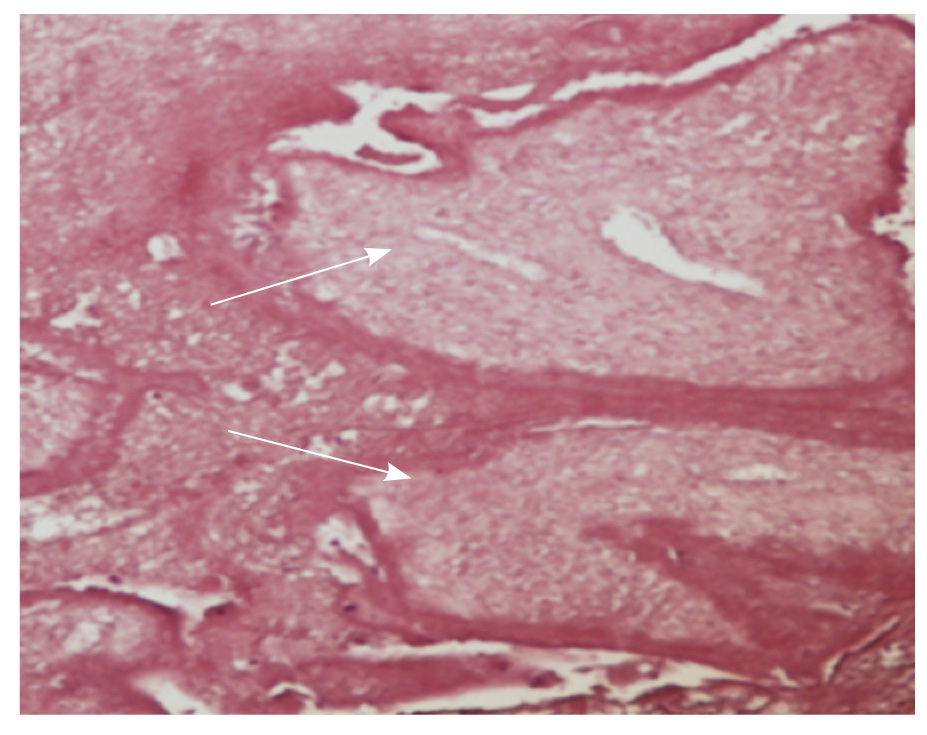

По данным гистологического исследования определялось врастание ворсин хориона первого триместра гестации в миометрий на всю глубину стенки матки до серозного покрова без прорастания последнего (placenta increta) (рис. 6).

Рис. 6. Микропрепарат. Ворсины хориона первого триместра с дистрофическими изменениями (отмечены стрелкой), замурованные в фибриновые массы в толще миометрия. Окраска гематоксилином и эозином; × 200